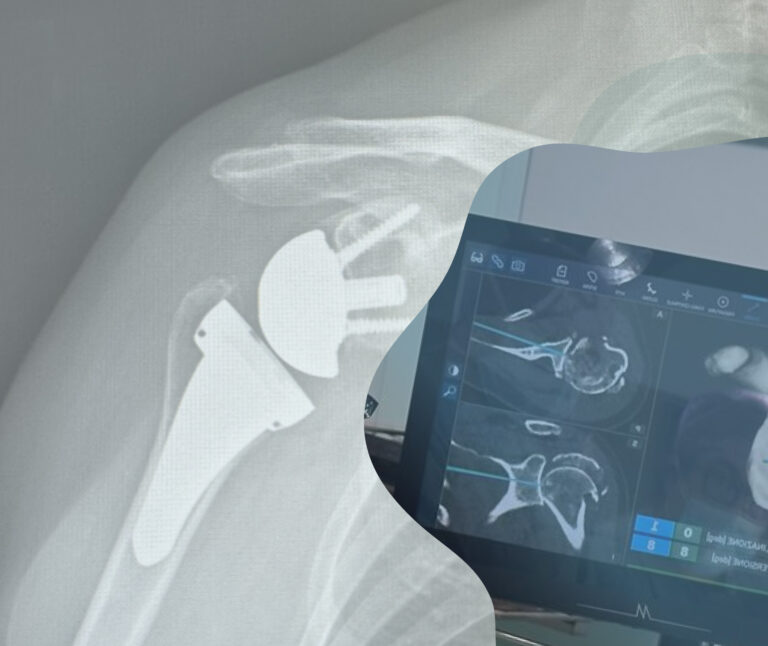

Chirurgia protesica: i vantaggi del sistema NextAR.